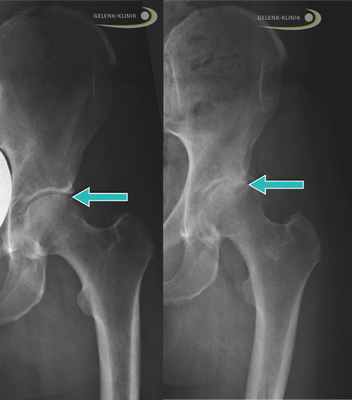

Слева: Рентген здорового бедра у взрослого. Стрелой отмечена суставная щель между крышей вертлужной впадины (Acetabulum) и головкой бедренной кости (Caput femoris). Справа: Рентген тазобедренного сустава, изменённого вследствие артроза, неравномерные высветления указывают на дегенеративные изменения. © Gelenk-Klinik